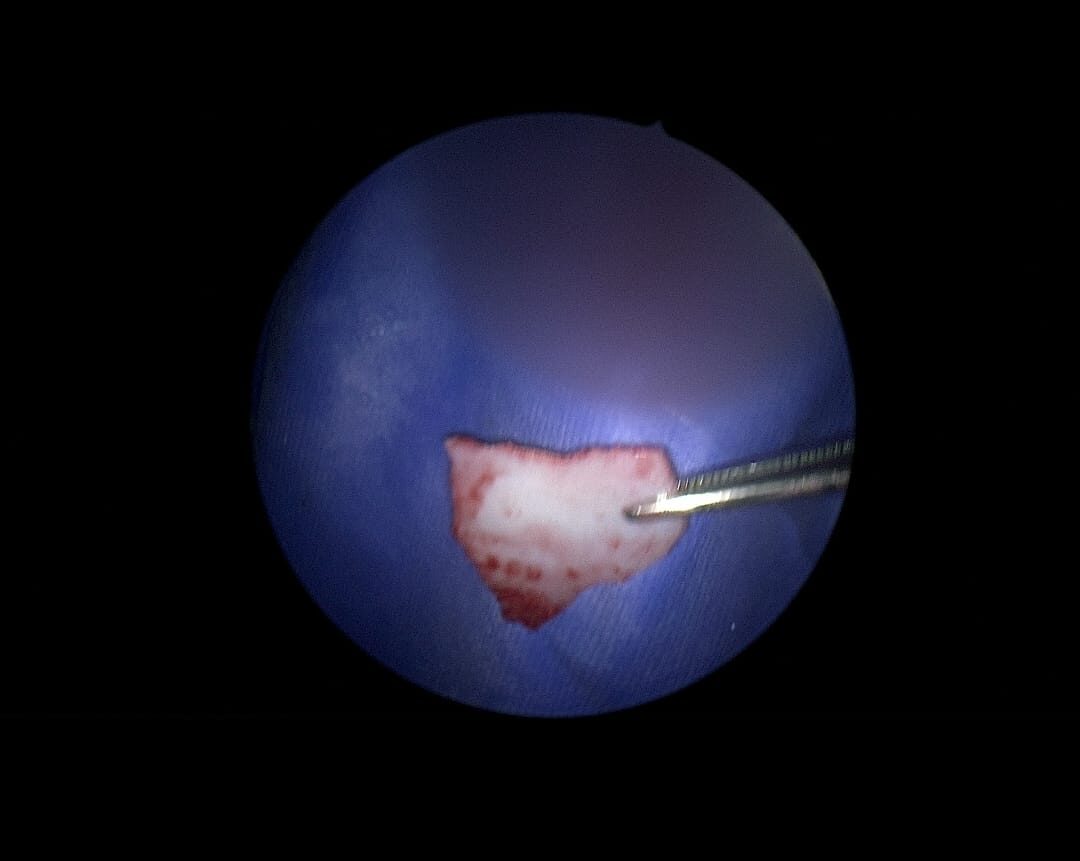

• ترقيع طبلة الأذن وإزالة تسوس الأذن بالمنظار والميكروسكوب

• استئصال لحميات الأنف والجيوب الأنفية

• استئصال لحميات الأحبال الصوتية